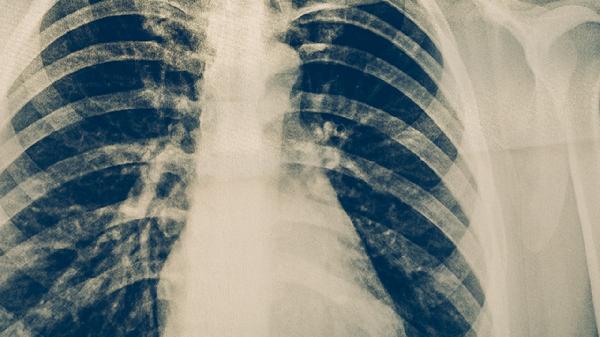

肺结核患者在治疗期间,饮食应遵循高蛋白、高维生素、易消化的原则。除了适量食用鱼类,还应保证足量的瘦肉、蛋类、奶制品及新鲜蔬菜水果的摄入。务必严格遵医嘱完成全程、规律的抗结核药物治疗,不可自行停药或更改剂量。定期复查肝肾功能、血常规及胸部影像学检查,监测病情变化和治疗反应。保持居住环境通风,注意个人卫生,适当休息,避免劳累,这些综合措施共同助力于疾病的康复。